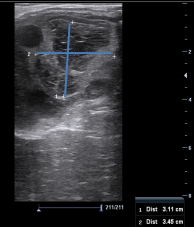

En hoppe er blevet scannet med henblik på insemination. Billedet viser venstre ovarie. De blå markeringer angiver målene på en struktur i ovariet på 35 x 31 mm. To dage før var der en follikel på 38 mm. Hvilken struktur ses på ovariet?

1 Granulosa-theca celle tumor

2 Follikelcyste

3 Luteincyste

4 Corpus hæmorrhagicum

Det rigtige svar er 4